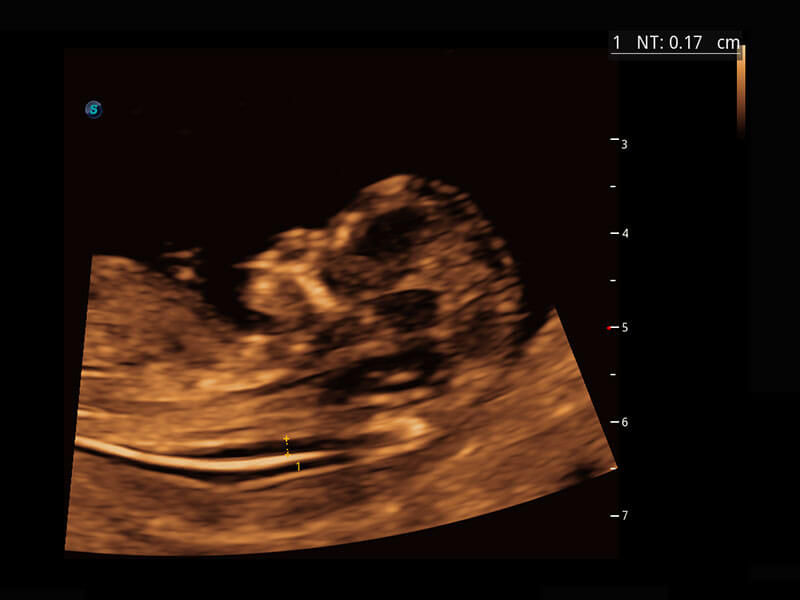

P60在胎儿早孕期超声筛查中为您带来优异的图像质量。

早孕-胎心

光影成像-孕囊